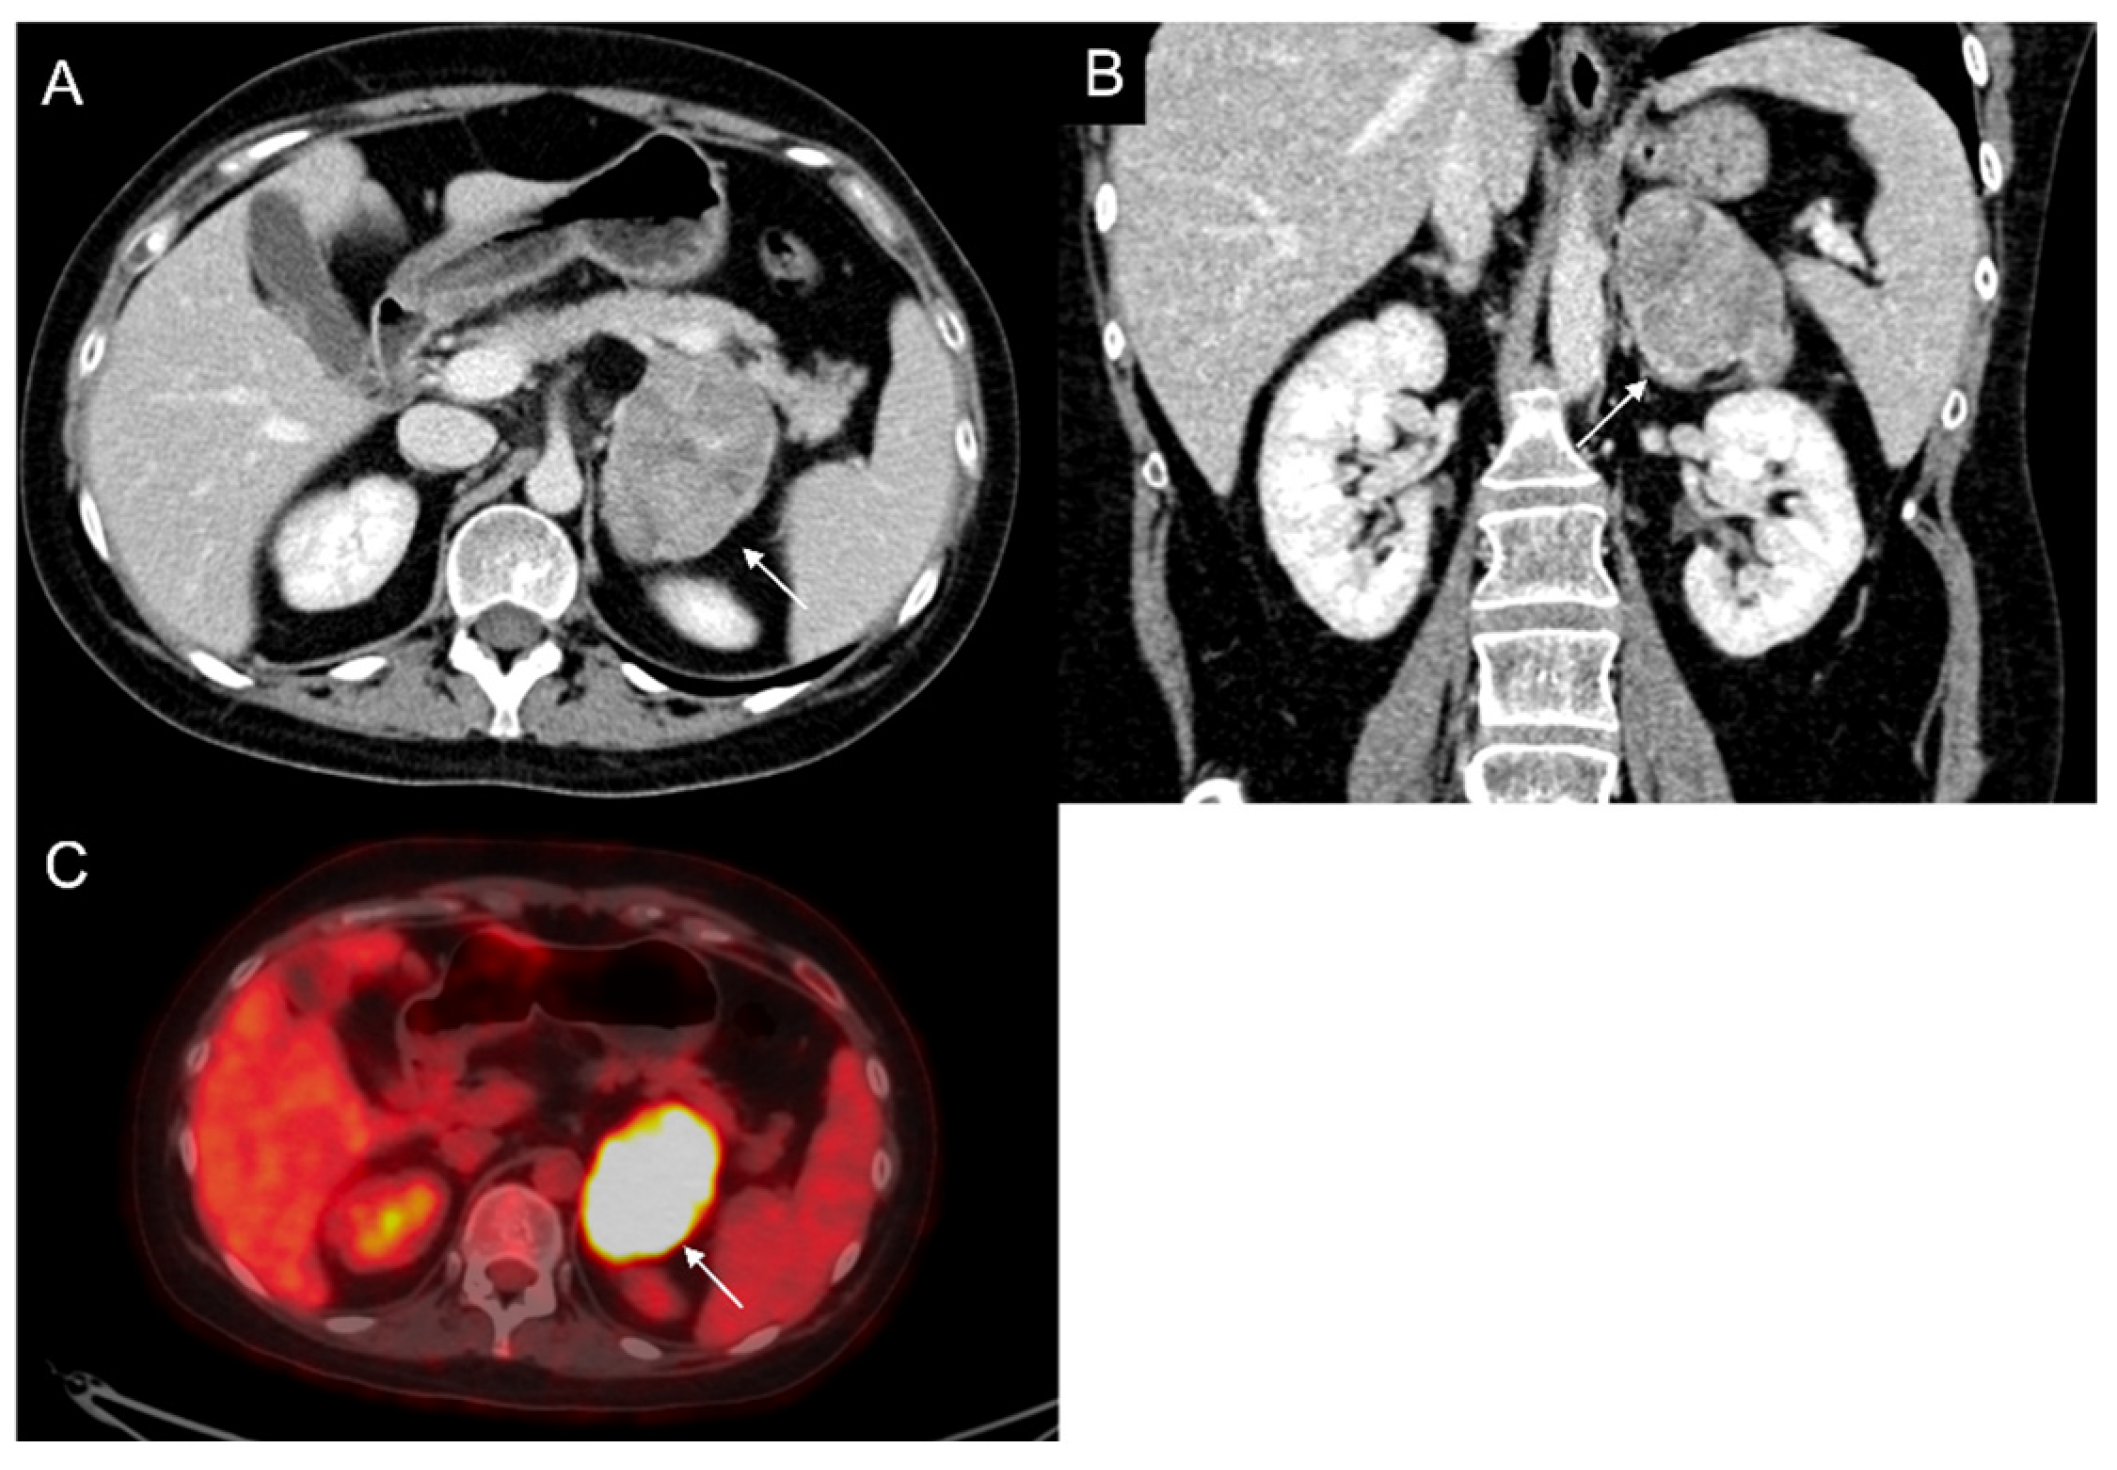

Figure 3.

60-year-old woman with history of breast cancer and adrenal metastasis. Left adrenal mass with inhomogeneous enhancement (arrow) on CT portal phase in axial (A) and coronal (B) planes, and positive PET (C).